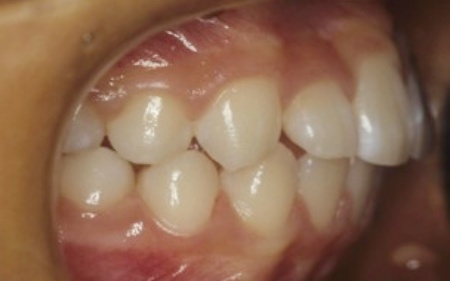

矯正治療終了後は、歯が元の位置に戻ろうとする後戻りを起こすリスクがありますが、治療後15年たった現在も後戻りすることなく、正しい歯並びを維持しています。

15年後の様子